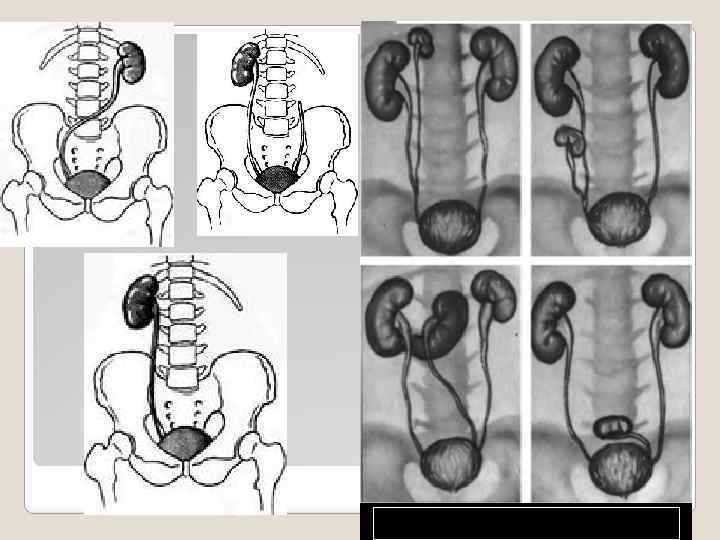

Перекрёстная дистопия - состояние, при котором обе почки расположены с одной стороны позвоночника, а мочеточник нижней из них перекрещивает позвоночный столб и впадает в мочевой пузырь в обычном месте.

Перекрёстная дистопия - состояние, при котором обе почки расположены с одной стороны позвоночника, а мочеточник нижней из них перекрещивает позвоночный столб и впадает в мочевой пузырь в обычном месте.

АНОМАЛИИ ВЗАИМООТНОШЕНИЯ Аномалии взаимоотношения - различные варианты сращений между обеими почками. В зависимости от взаимоотношения продольных осей почек принято различать S-образную, Lобразную, I-образную, галетообразную и подковообразную деформации почек.

АНОМАЛИИ ВЗАИМООТНОШЕНИЯ Аномалии взаимоотношения - различные варианты сращений между обеими почками. В зависимости от взаимоотношения продольных осей почек принято различать S-образную, Lобразную, I-образную, галетообразную и подковообразную деформации почек.

При подковообразной почке почки срастаются одноимёнными полюсами (в 90% случаев - нижними). Порок встречается с частотой 1: 400 новорождённых. Подковообразная почка чаще эктопирована, её перешеек расположен на уровне IV или V поясничного позвонка. Почечные артерии обычно отходят от аорты, но уровень их отхождения тем ниже, чем более выражена почечная эктопия. Вследствие малой подвижности подковообразная почка более подвержена травмам. Характерно, что мочеточники при этом пороке перегибаются через паренхиму, что приводит к нарушениям уродинамики на уровне ЛМС. Здоровая подковообразная почка иногда проявляется болезненными ощущениями в животе вследствие сдавления других органов.

При подковообразной почке почки срастаются одноимёнными полюсами (в 90% случаев - нижними). Порок встречается с частотой 1: 400 новорождённых. Подковообразная почка чаще эктопирована, её перешеек расположен на уровне IV или V поясничного позвонка. Почечные артерии обычно отходят от аорты, но уровень их отхождения тем ниже, чем более выражена почечная эктопия. Вследствие малой подвижности подковообразная почка более подвержена травмам. Характерно, что мочеточники при этом пороке перегибаются через паренхиму, что приводит к нарушениям уродинамики на уровне ЛМС. Здоровая подковообразная почка иногда проявляется болезненными ощущениями в животе вследствие сдавления других органов.